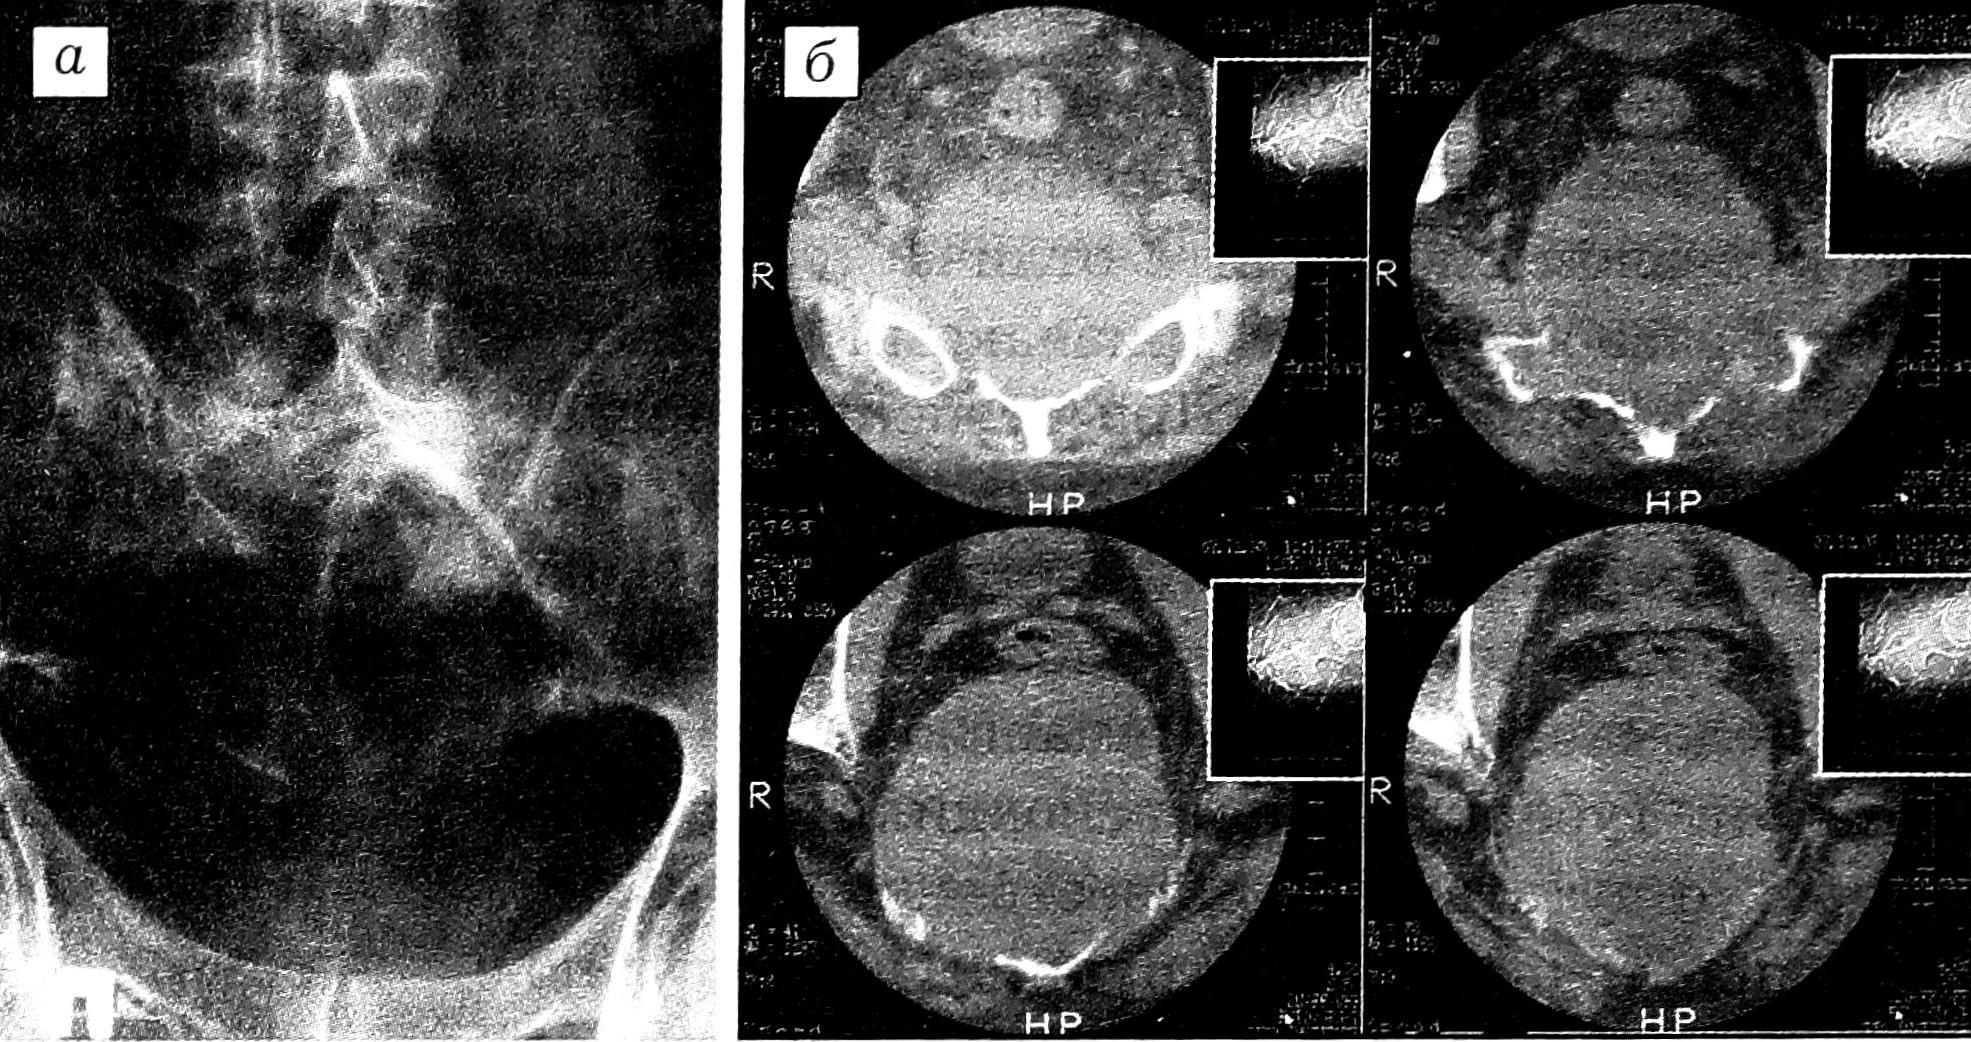

Рис. 2. Больной М., 40 лет. Диагноз: хордома S1-S5. КТ.

Остеолитическая деструкция крестца и его боковых масс. Огромный внутритазовый мягкотканный компонент опухоли, смещающий прямую кишку кпереди. По периферии опухоли отдельные обызвествления.

Рис. 3. Больной М., 43 лет. Диагноз: злокачественная остеобластокластома крестца.

a — обзорная рентгенограмма в прямой проекции; б — КТ: остеолитический очаг деструкции крестца и его боковых масс с внутритазовым компонентом, отдельные участки обызвествления и костеобразования в толще опухоли.